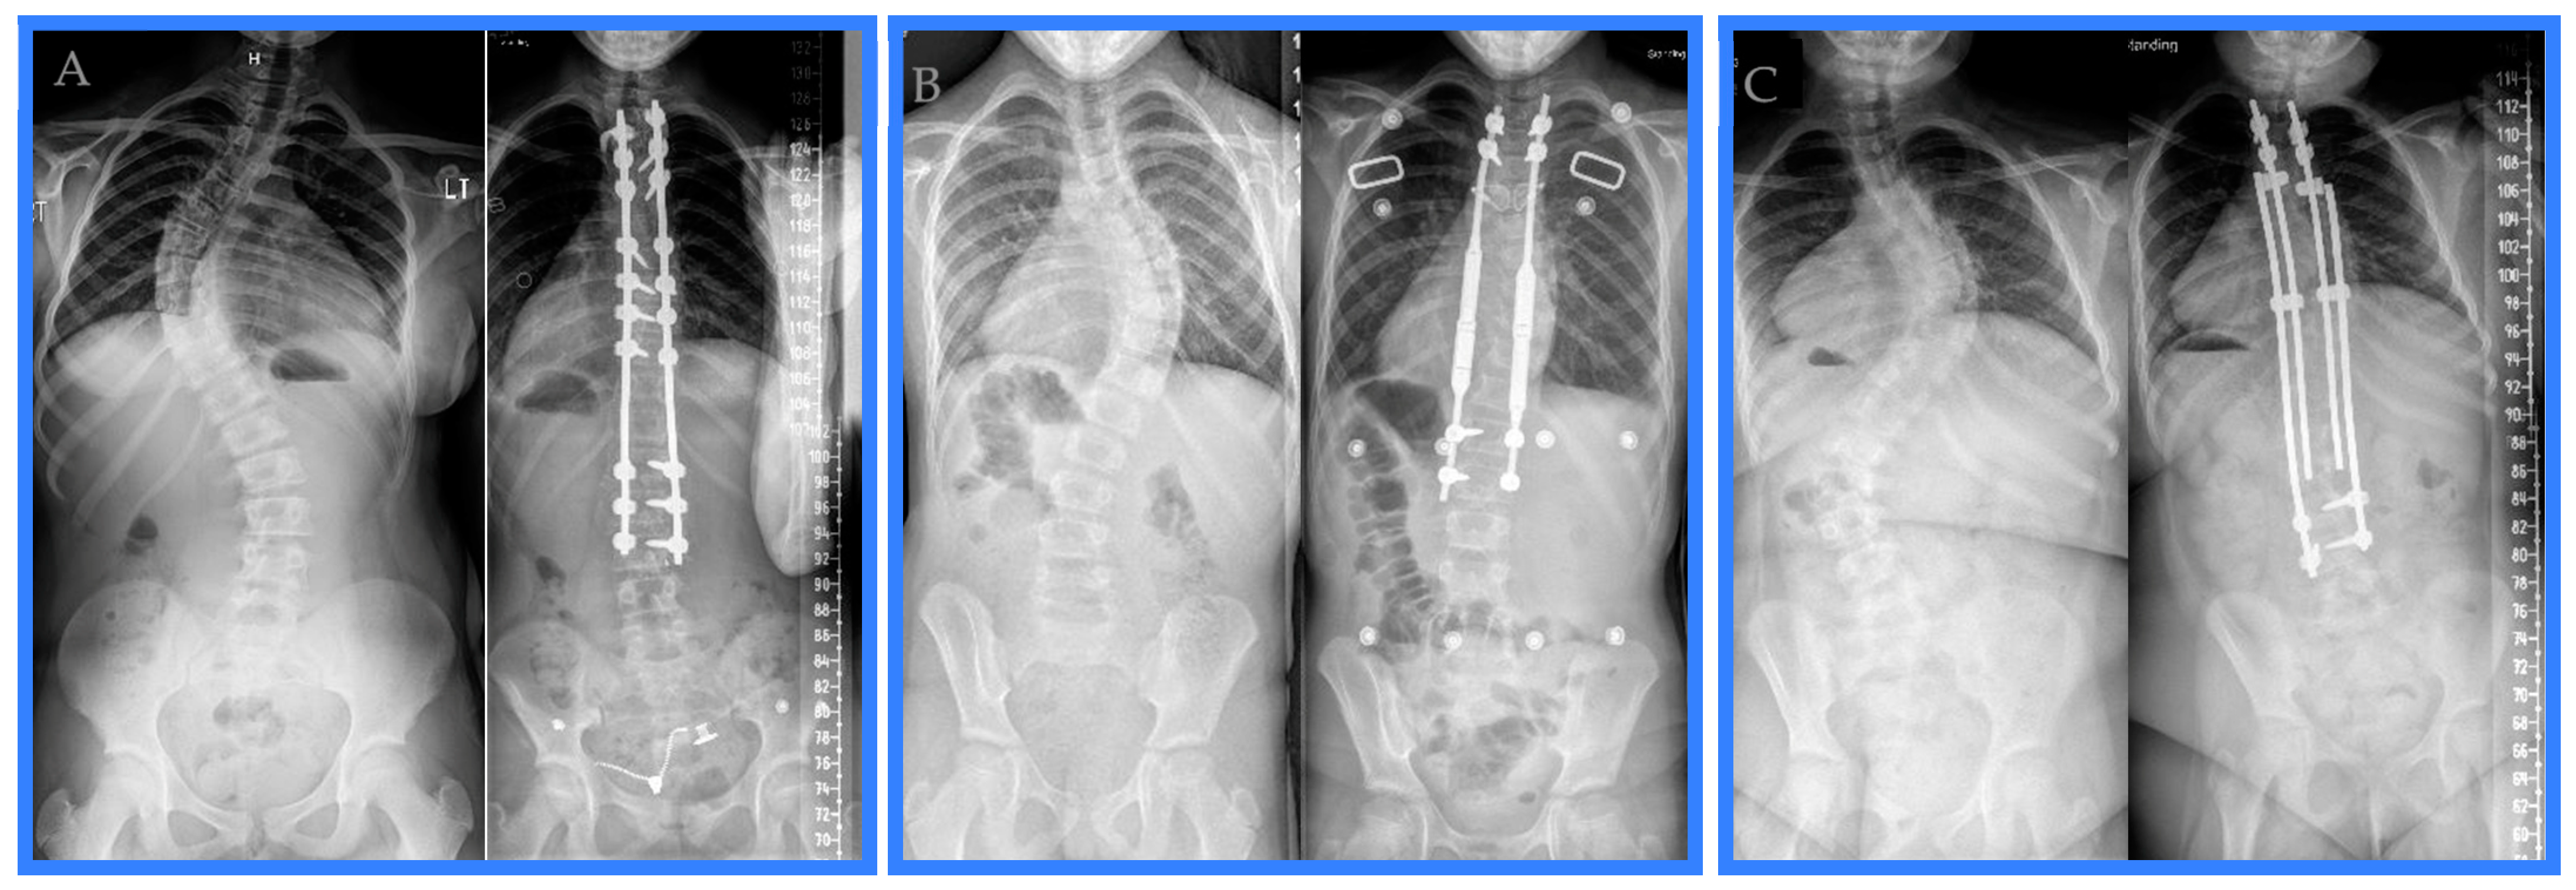

Variations existed among the posterior spinal fusions performed for surgical management of juvenile idiopathic scoliosis during the study period. The lengths of the posterior spinal fusion constructs ranged from 11 to 14 vertebrae. The construct length was 13 vertebrae 40% of the time, 14 vertebrae in 26% of posterior spinal fusions, 11 vertebrae 17% of the time, and 12 vertebrae in the remaining 17% of cases. The upper instrumented vertebra was instrumented with a hook over the transverse process in all but one posterior spinal fusion. In the case that did not utilize hooks on the upper instrumented vertebra, pedicle screws were used as the most superior instrumentation. T3 was the most common upper instrumented vertebra (70%). The next most common upper instrumented vertebra was T2 (26%), and only one construct (4%) utilized T4 as the upper instrumented vertebra. The lowest instrumented vertebra was more variable, with ten constructs utilizing L3 (43%), five stopping at L4 (22%), four ending at L1 (17%), two constructs going to T12 (9%), and two constructs finishing at L2 (9%). Two constructs utilized a combination of pedicle screws and sublaminar wires to anchor the rods; otherwise, the posterior spinal fusion constructs were dual rods affixed to the spine with a mix of intermittent uniaxial and polyaxial pedicle screws. Examples of the posterior spinal fusion, the magnetically controlled growing rod, and the traditional growing rod constructs are provided (see Figure 1).

Figure 1. Pre-operative and first post-operative appointment radiographs exemplifying a (A) posterior spinal fusion, (B) magnetically controlled growing rod, and (C) traditional growing rod treatment of juvenile idiopathic scoliosis during the study period.